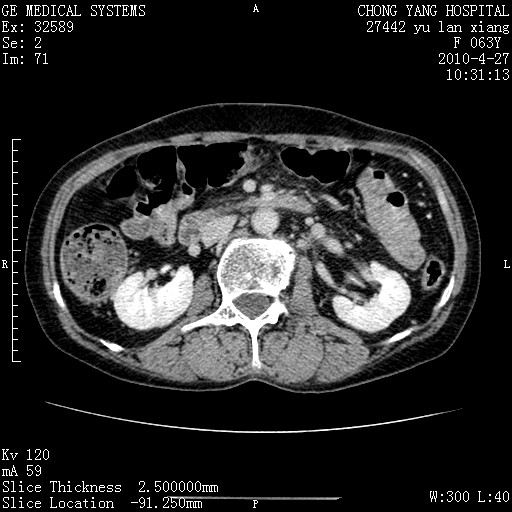

标题: CT26066:F63Y 上腹正中压痛半月,CA199:7400u/ml,MR示胰腺炎伴 [打印本页]

胰腺癌侵犯腹腔动脉干-分支、胃壁、左侧膈肌伴胰周及腹膜后淋巴结转移、胆囊切除术后。

胰腺癌侵犯腹腔动脉干-分支、胃壁、左侧膈肌伴胰周及腹膜后淋巴结转移、胆囊未显影。